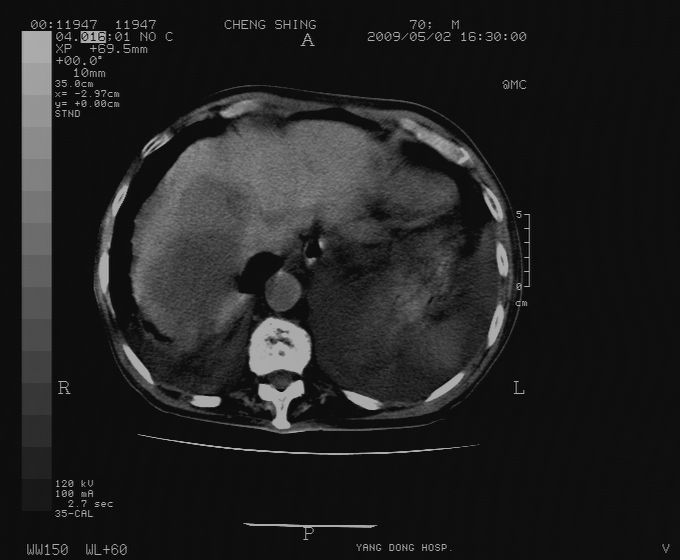

标题: CT19743:男70岁,肺部疾病入院,B超发现肝右叶占位,CT [打印本页]

标题: CT19743:男70岁,肺部疾病入院,B超发现肝右叶占位,CT

肝表面塌陷,病灶周围有子灶,前面较大子灶强化符合肝癌表现,考虑肝癌肝转移可能性大.

1.考虑肝癌肝转移

2.两侧胸水,左下肺不张!

1)考虑肝癌并肝内转移。2)少量腹水。3)双侧胸腔积液。

1)考虑肝癌并肝内转移。2)少量腹水及双侧胸腔积液。3)椎体退变。